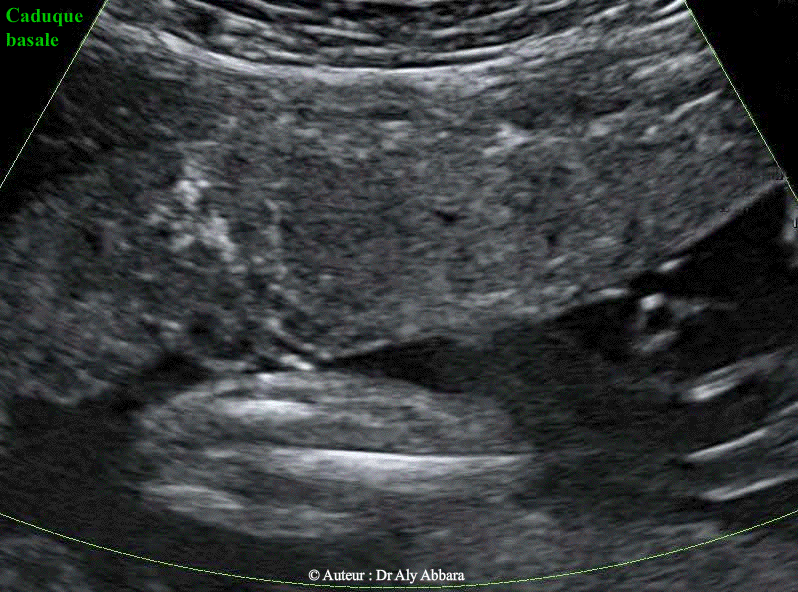

• Images échographiques par voie transpariétale abdominale mettant en évidence l’aspect habituel et normal de la zone de l'insertion du placenta sur la paroi de l'utérus :

Sur une coupe parfaitement sagittale (plan vertical, perpendiculaire au plan vu de face de la paroi utérine et du placenta) on peut distinguer quatre couches distinctes :

• I- La paroi abdominale de la femme enceinte

• II- La paroi de l'utérus (le myomètre)

III- Le placenta

• IV- Puis entre le myomètre et le placenta on peut observer la présence d'un liseré hypo-an-échogène séparant le myomètre du placenta ; ce liseré correspond anatomiquement à la caduque basale et son riche réseau veineux qui constituent le plan de clivage physiologique du placenta lors de la délivrance.

Un des signes évoquant le diagnostic de " placenta accreta " est la disparition de ce liseré, car cela témoigne de la disparition de la caduque basale et l'insertion directe des villosités trophoblastiques sur le myomètre (un organe juxtaposé en particulier la vessie quand il s'agit de placenta praevia antérieur percreta).

Les images publiées dans cette page ont été réalisées chez une femme enceinte de 28 semaines d'aménorrhée.